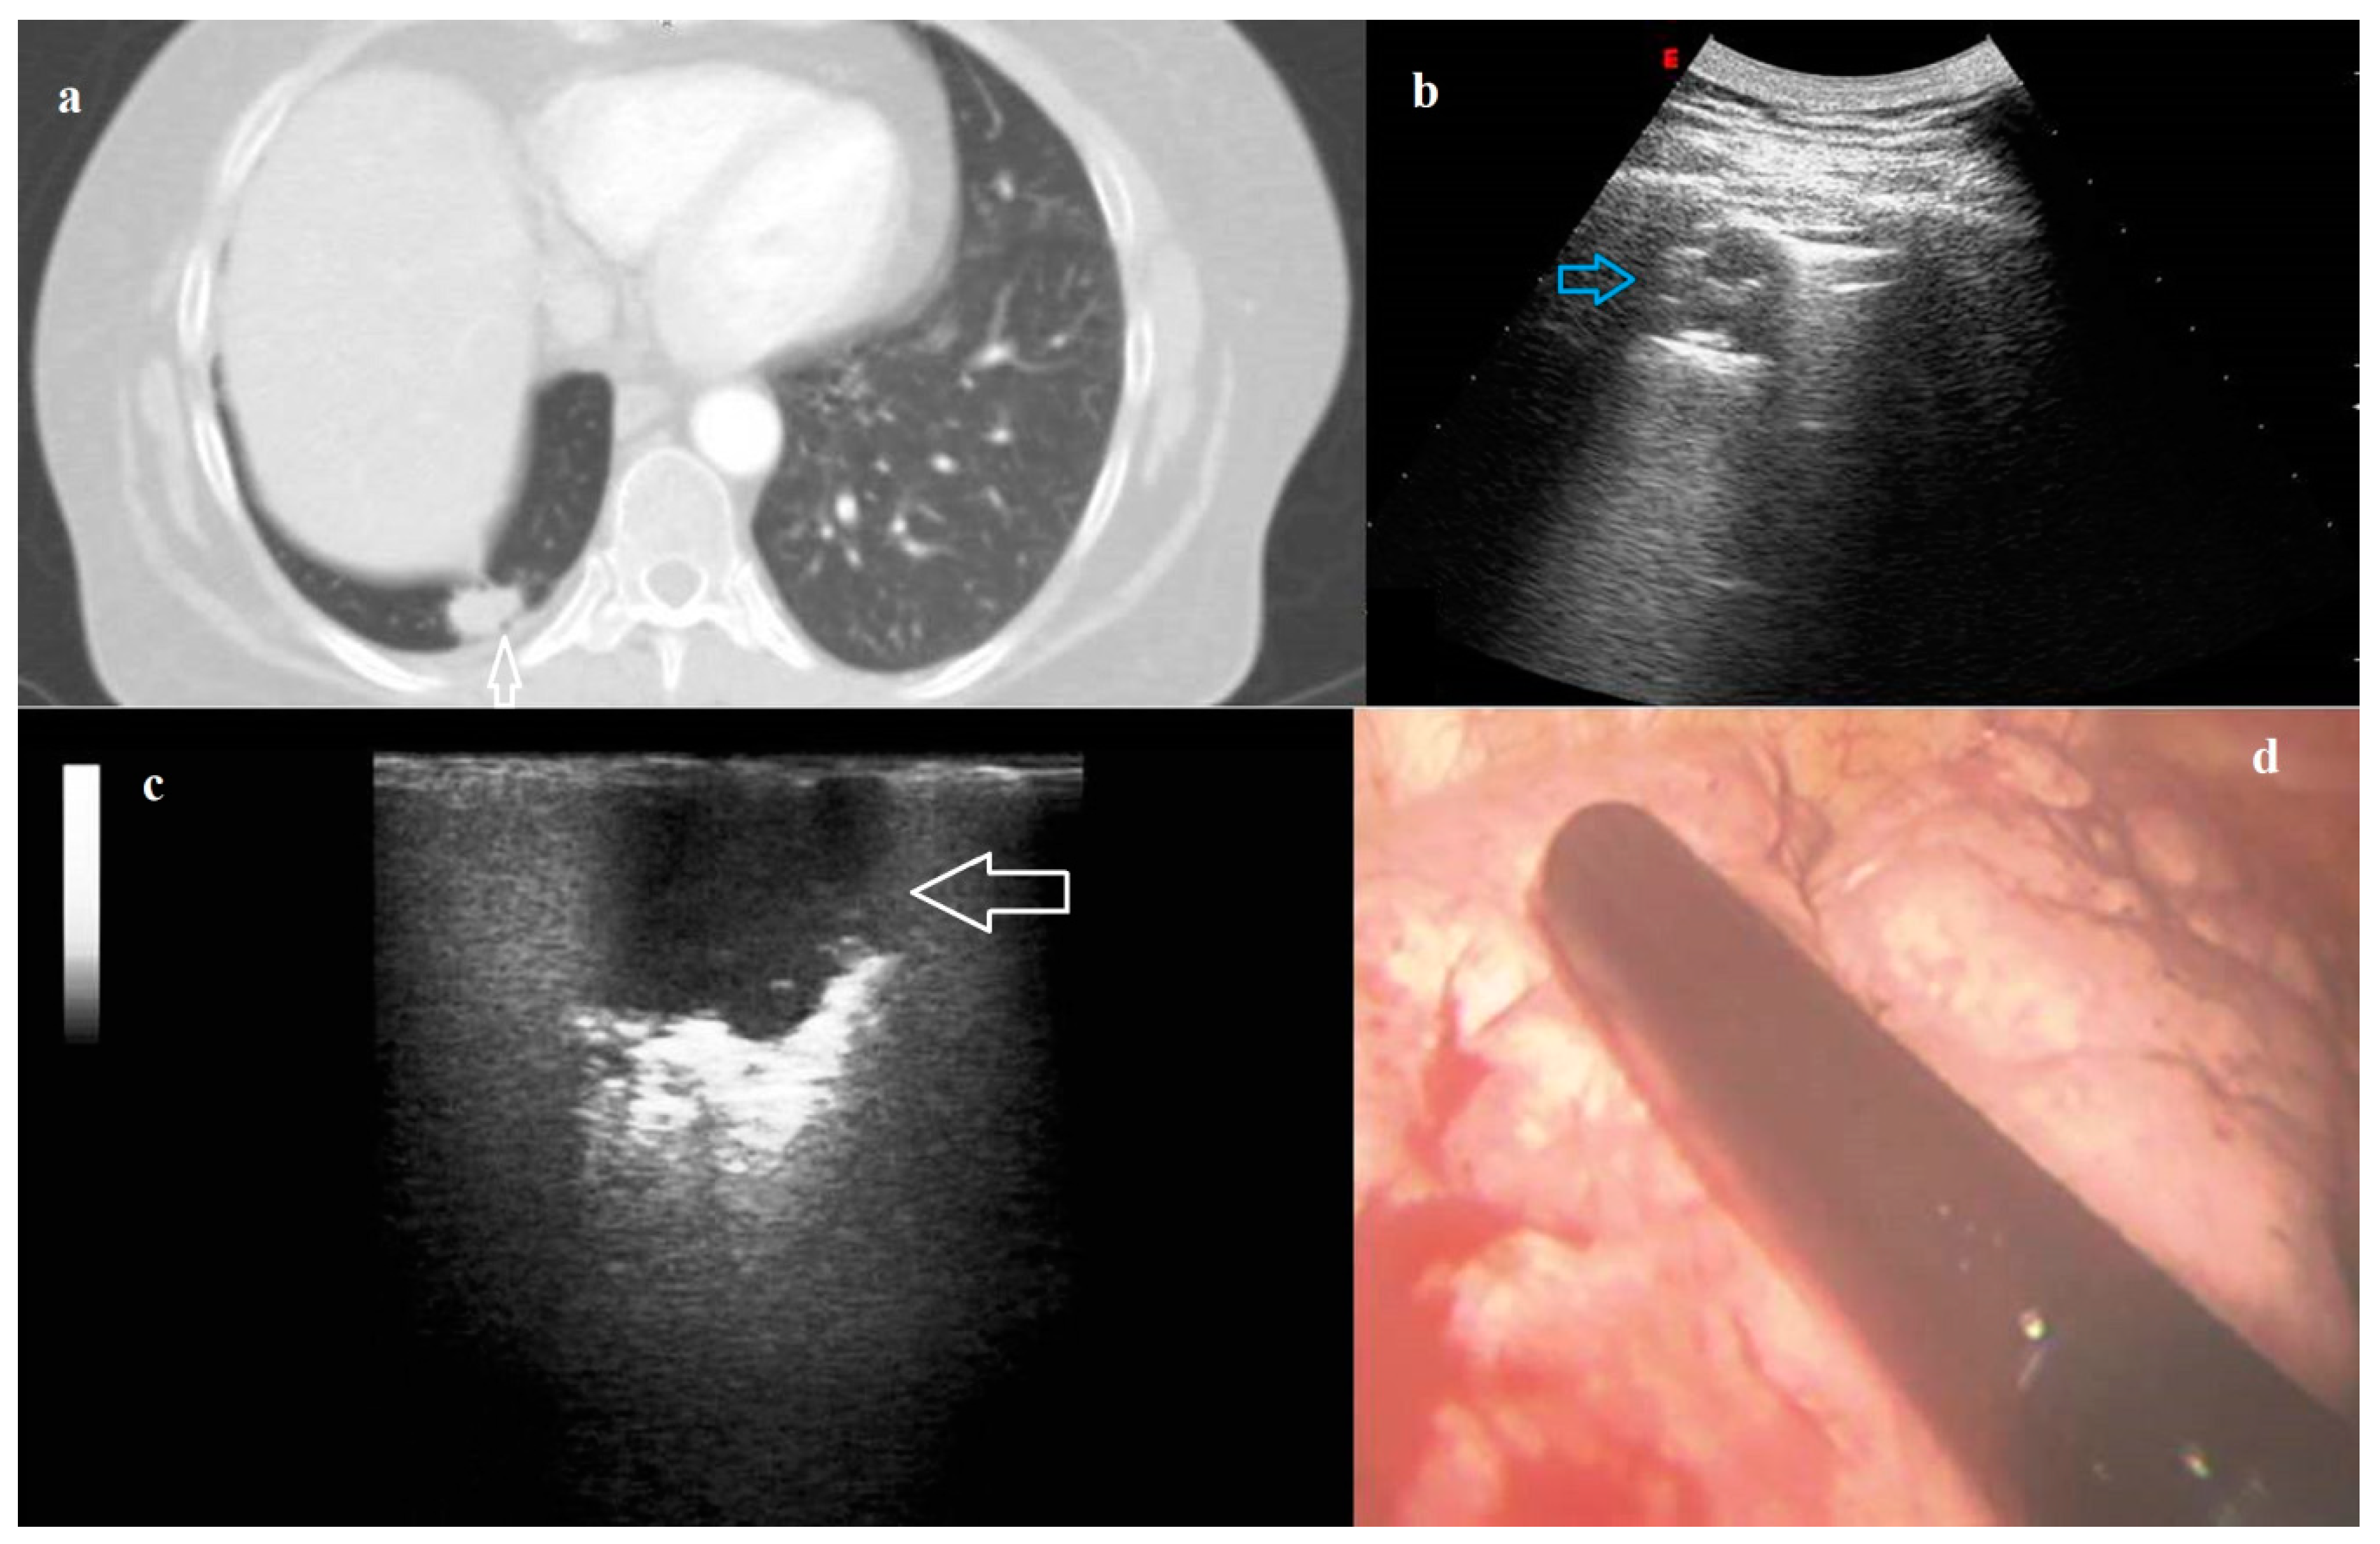

VATS was performed in 49/131 (37.40%) patients, while open thoracotomy in 82/131 (62.60%) patients. 124/131 nodules (94.66%) were identified at digital palpation. The visualization of nodules was allowed by ILU in all the cases (100.00%). In addition, it was possible to detect by ILU also two CT-detected nodules (maximum diameter 9.00 mm and 7.00 mm, respectively) not visualized during surgery nor identified by manual palpation (Figure 1). The final histological diagnoses of the two nodules were hamartochondroma and histiocytosis x, respectively.

Figure 1. (a) Axial Chest Computed Tomography (CT) scan showing a not subpleural micronodule (blue arrow) in the left lung (maximum diameter 7.00 mm) not visualized during surgery nor identified by manual palpation. (b) Photograph showing the intracavitary laparoscope probe (8–12 MHz) placed on the left lung during Video-Assisted Thoracoscopic Surgery (VATS). (c) Intraoperative lung ultrasound during VATS (VAT-US) showing the pulmonary nodule (white arrow) with a hypoechoic US pattern, regular rounded shape and well-defined margins. The final Histological diagnosis was pulmonary Langerhans cell histiocytosis X.